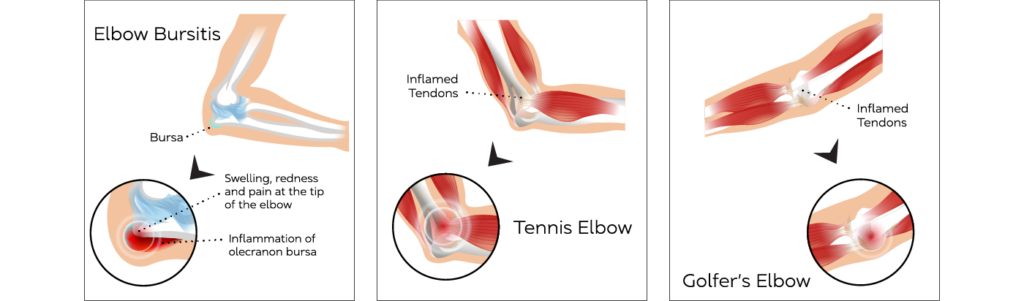

Olecranon Bursitis

Olecranon Bursitis is caused by the inflammation of the fluid sac that is between the olecranon (point of the elbow) and the skin.

Olecranon Bursitis is a common condition.

Common symptoms include localised swelling and tenderness, pain on movement, and redness.

Ultrasound guided aspiration (removal of fluid) followed by injection of local anaesthetic combined with corticosteroid often gives a large amount of symptomatic pain relief.

Tennis elbow

When tendons in the elbow are overloaded and repeatedly used, a person can develop a Tennis Elbow.

Tennis Elbow is common in people who have jobs that require repetitive motions of the arm and wrist.

Tennis elbow symptoms include pain and tenderness of the bone on the outside of the elbow. The pain may radiate into the upper or lower arm, with pain on hand movements like gripping, holding objects and turning door knobs.

Ultrasound can be used to identify and confirm the condition. An ultrasound guided injection using steroids, hyaluronic acid or regenerative medicine products can be offered as treatment.

Golfer's elbow

Golfer’s Elbow is a condition that causes pain and inflammation in the tendons connecting the forearm to the elbow.

Golfer’s Elbow is common in people who go from rarely using their forearm muscles to using them a lot.

The most common signs of Golfer’s Elbow are pain and tenderness on the inner side of the elbow that can extend along the forearm, a general stiffness of the elbow, weakness in the wrists and hands and a possible numbing sensation or tingling in the joint.

Ultrasound can be used to identify and confirm the condition. An ultrasound guided injection using steroids, hyaluronic acid or regenerative medicine products can be offered as treatment.